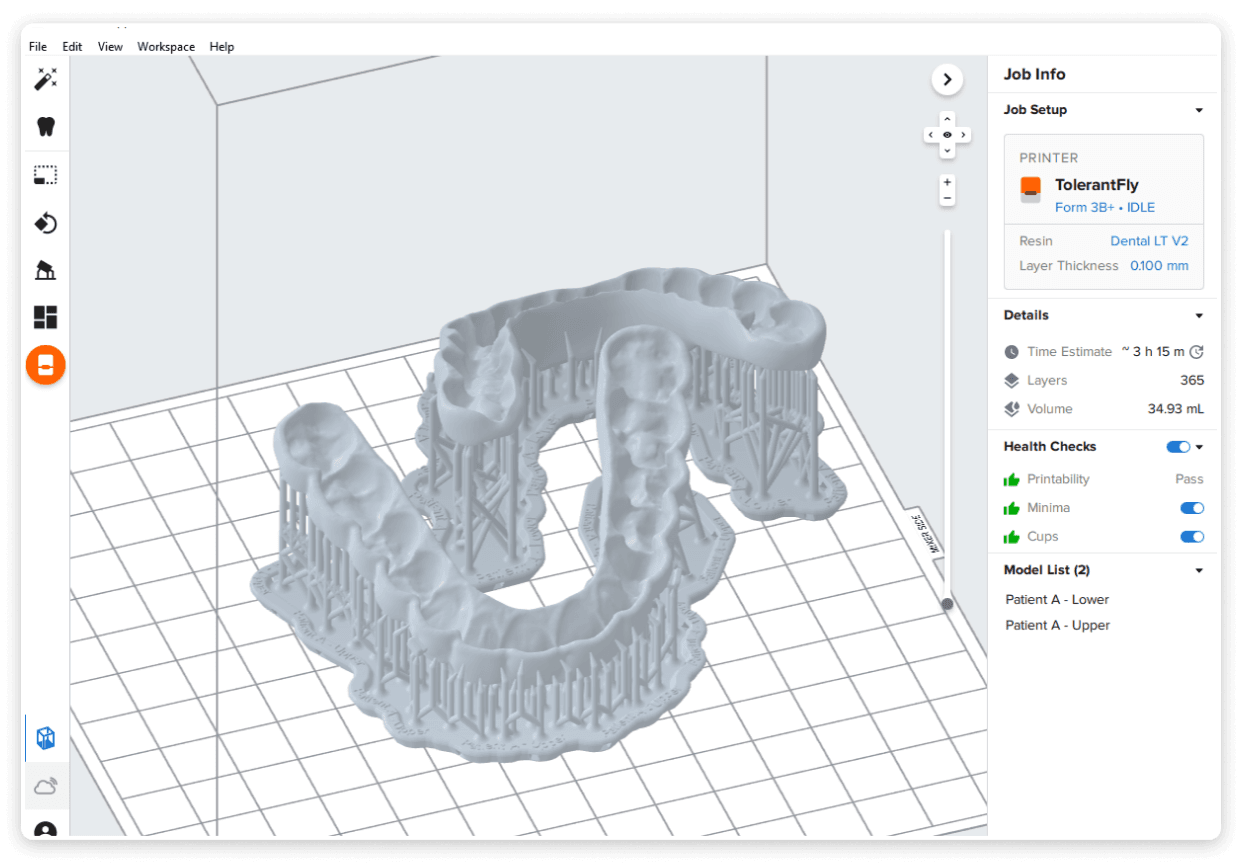

Planmeca Romexis® Smart are artificial intelligence (AI) tools for its Planmeca Romexis software platform. The feature allows the segmentation and recognition of anatomies, such as teeth, nerves, jaws, airways, and sinuses. This enables easier and faster use of the software and excellent visualization of the case for patient education. With the help of AI, CBCT images and intraoral scans are automatically mapped. Thanks to the automatic tooth number recognition, a CBCT volume can be easily navigated just by clicking on the tooth number in the tooth chart, and the software centers all views on the tooth of interest.